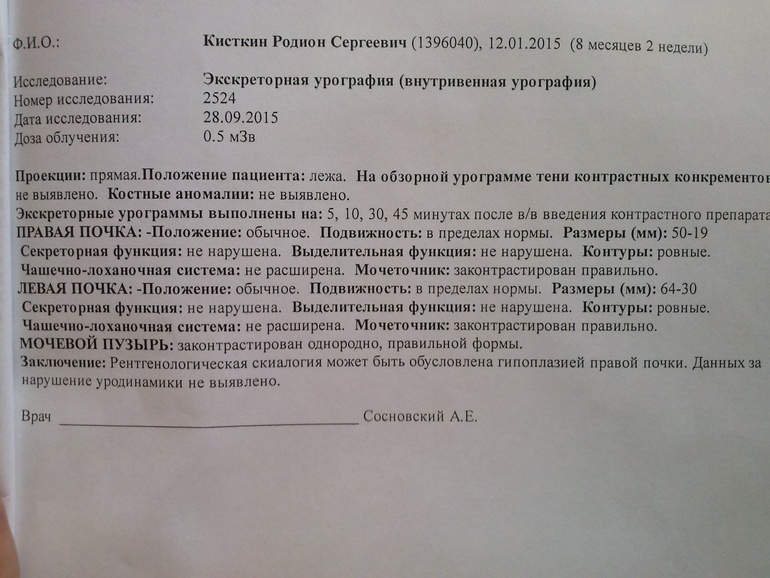

Медицинские изображения и примеры эксреторной цистографии